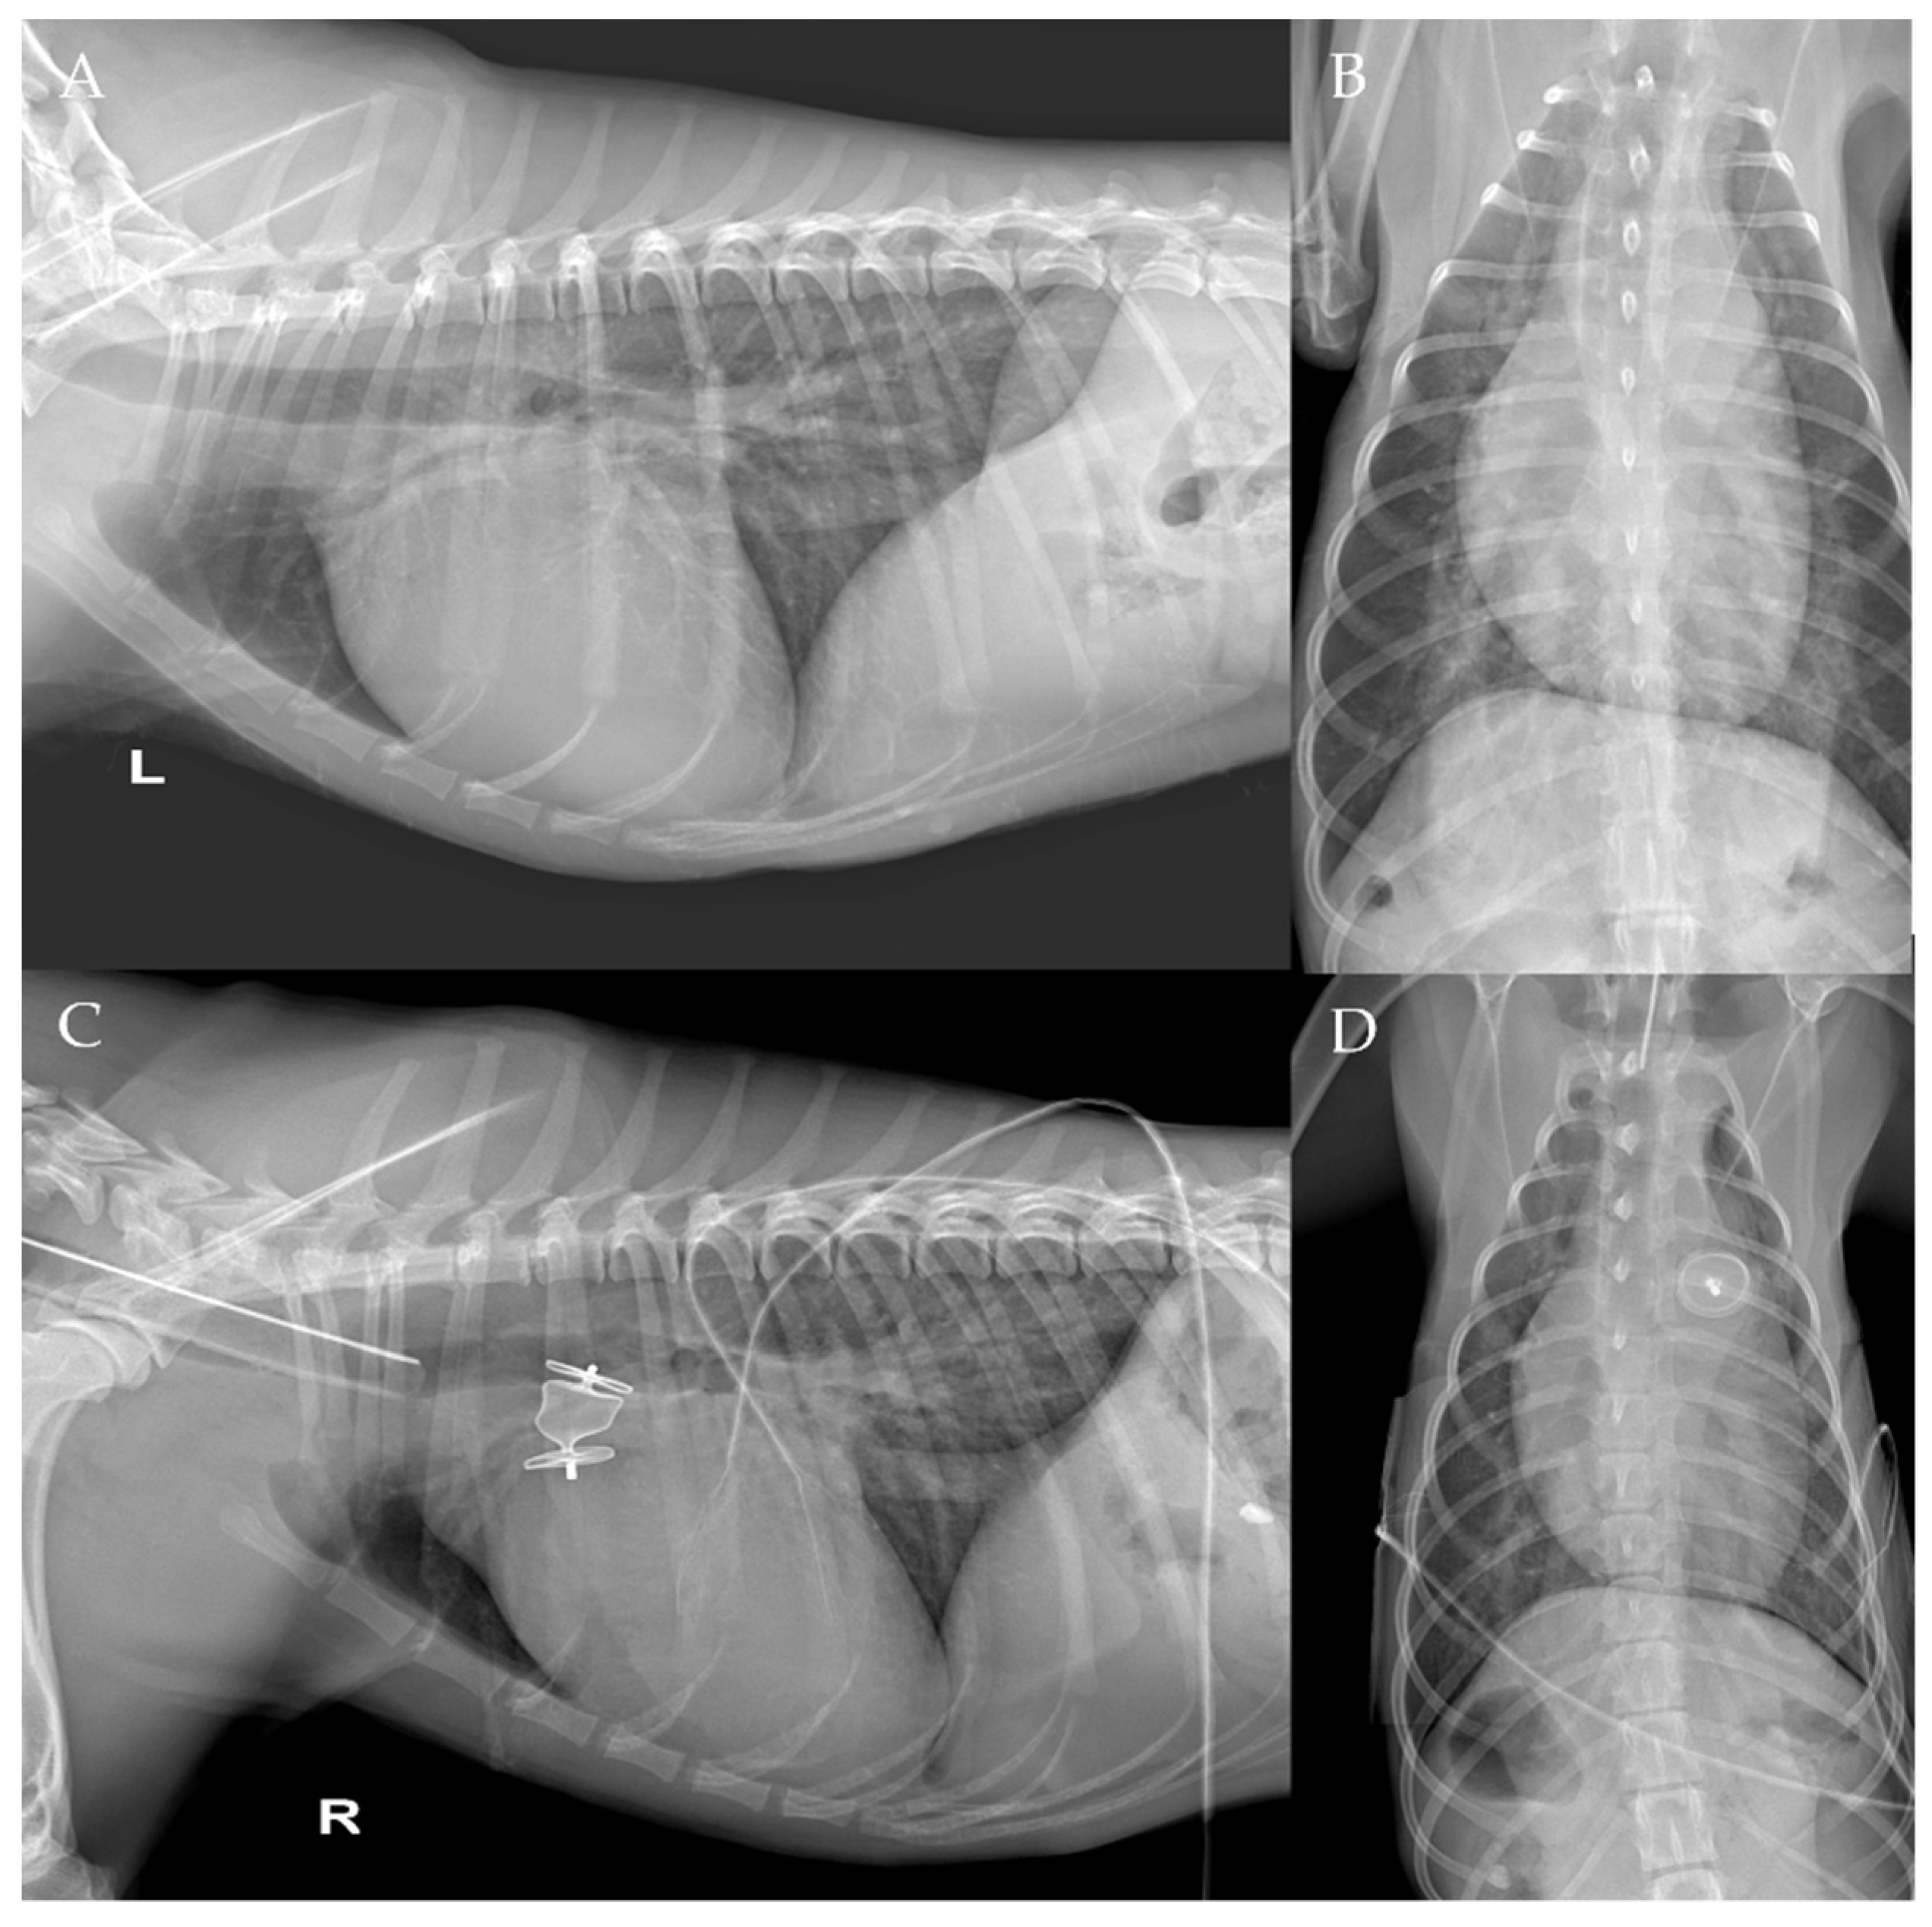

The thoracic radiographs performed before and just after the procedure showed a reduction in the cardiac silhouette as well as significant reduction of the over-circulation vascular pattern for all dogs (Figure 8, Figure 9, Figure 10, Figure 11 and Figure 12).

Figure 8. Pre-procedure (A,B) and post-procedure (C,D) left lateral and dorso-ventral thoracic radiographs of Case 1. L: left; R: right.